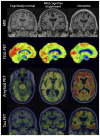

Figure 2-4

Progression of imaging features from cognitively normal to mild cognitive impairment to dementia. FDG-PET = fluorodeoxyglucose positron emission tomography; MRI = magnetic resonance imaging; PET = positron emission tomography.